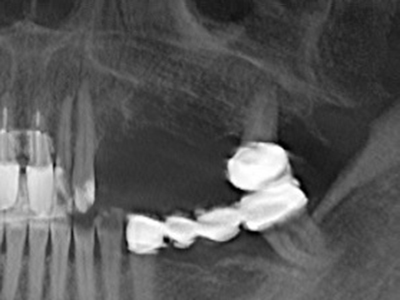

Fig. 13: Adequate irrigation with the 4-mm residual bone width is essential for this 52-year-old patient during the bone splitting.

Fig. 14: Placement of four tapered RSX implants (Bego Implant Systems, Bremen).

Fig. 15: The one-year follow-up x-ray examination shows stable conditions at the bone level.

Fig. 16: The intraoral conditions are also stable with embedding of the implants in keratinized gingiva.